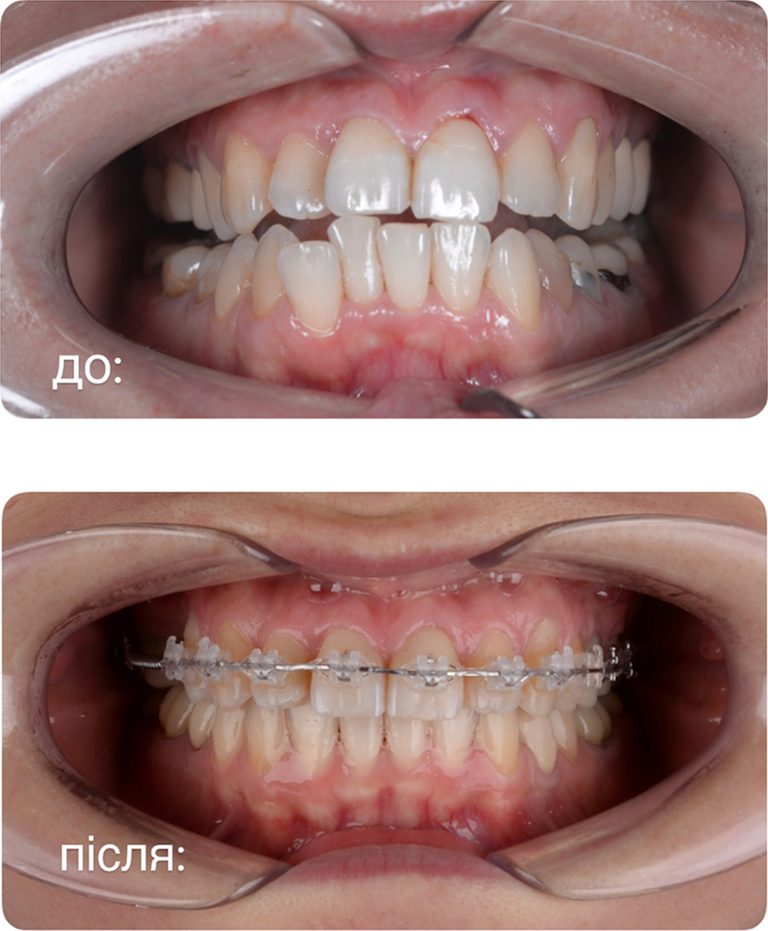

- straighten the dentition, correct the bite

ORTHODONTICS

Make your smile straight and white with help of aligners or brackets